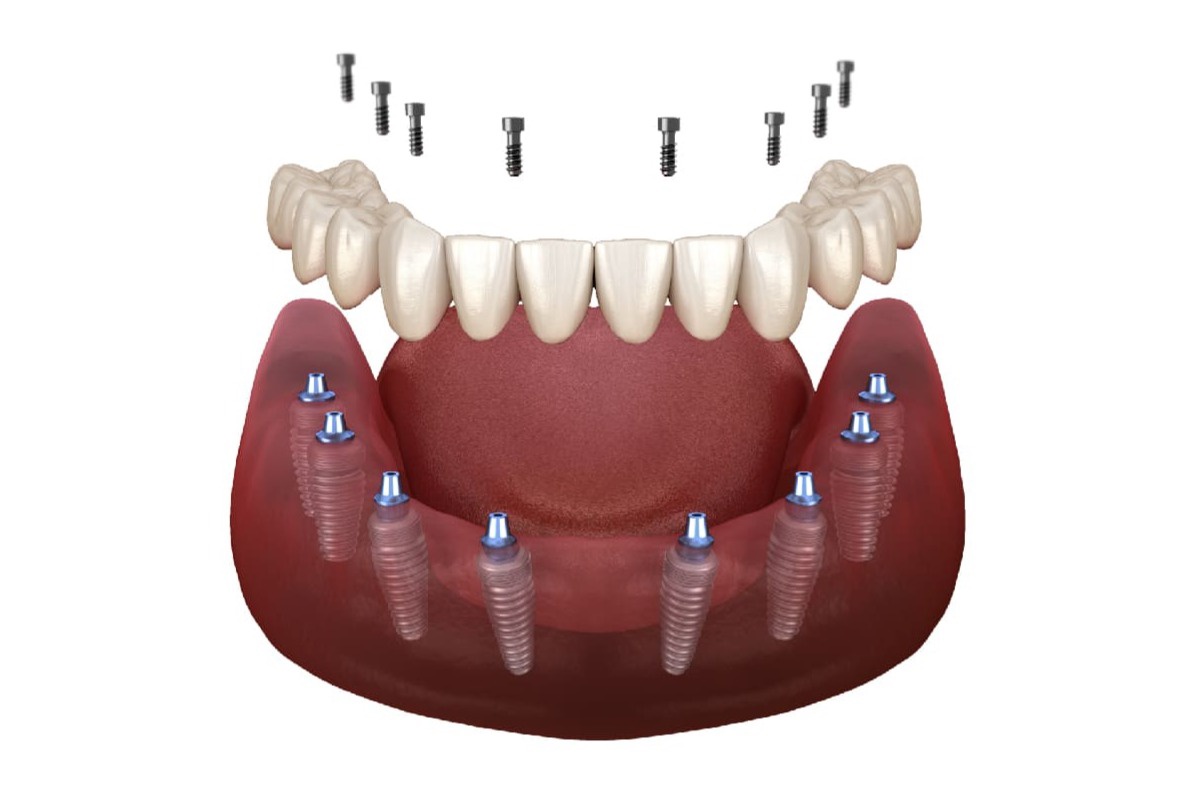

8+4天使之橋,概念和6+6天使之橋相同,8+4天使之橋意思是指8顆植牙牙冠搭配額外4顆牙橋式牙冠,以單顎12顆牙冠的方式進行全口重建;其中8支植體能讓單一顆植體所支撐的骨頭受力更平均。關於8+4天使之橋價格,只需新台幣34萬8千元,就能快速重建咬合享受美食!

越是宏偉的大樹,它的樹根必定越多越廣,那麼全口重建怎麼做才能像大樹一樣穩固呢?8+4天使之橋利用平均間隔的8支植體讓地基更穩建,骨頭受力也更平均,讓每一段牙橋不僅能更密合牙齦,也都能更平穩的相接,達到穩固且耐用的效果。在骨頭條件允許的情況下,8+4天使之橋當日就能有牙,且比多顆植牙累計下來的費用更便宜。透過專業醫師幫您分析,依照個人口腔條件評估、身體健康狀況、經濟考量、個人期待與需求等,消費者可選擇8+4天使之橋、6+6天使之橋或其他全口重建方式來解決整排缺牙的問題。